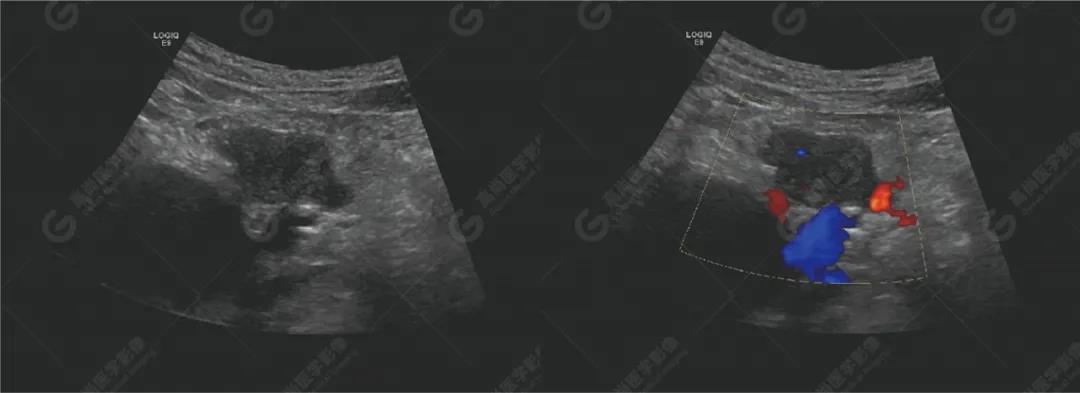

超聲檢查所見胰腺形態(tài)不規(guī)則,胰頭探及兩個實(shí)性低回聲團(tuán),大小分別約48mm×22mm、30mm×23mm,邊界不清,形態(tài)不規(guī)則,內(nèi)回聲欠均勻,CDFI顯示內(nèi)部可見少許血流信號。主胰管無擴(kuò)張。

肝門處探及一大小約66mm×40mm的梭形無回聲,上方與膽總管相連,下方顯示不清,壁光滑,內(nèi)透聲好,未見明顯異?;芈?,CDFI顯示內(nèi)未見血流信號。肝內(nèi)膽管左支稍擴(kuò)張,呈平行管征。

腹膜后可見數(shù)個低回聲,較大約25mm×13mm,邊界清,形態(tài)不規(guī)則,部分相互融合,CDFI顯示其內(nèi)可見點(diǎn)狀血流信號。

提示胰腺實(shí)性占位性病變(考慮胰腺癌)

腹膜后淋巴結(jié)腫大(考慮轉(zhuǎn)移性)

肝門囊性占位(先天性膽總管囊腫?)

肝內(nèi)膽管局部稍擴(kuò)張